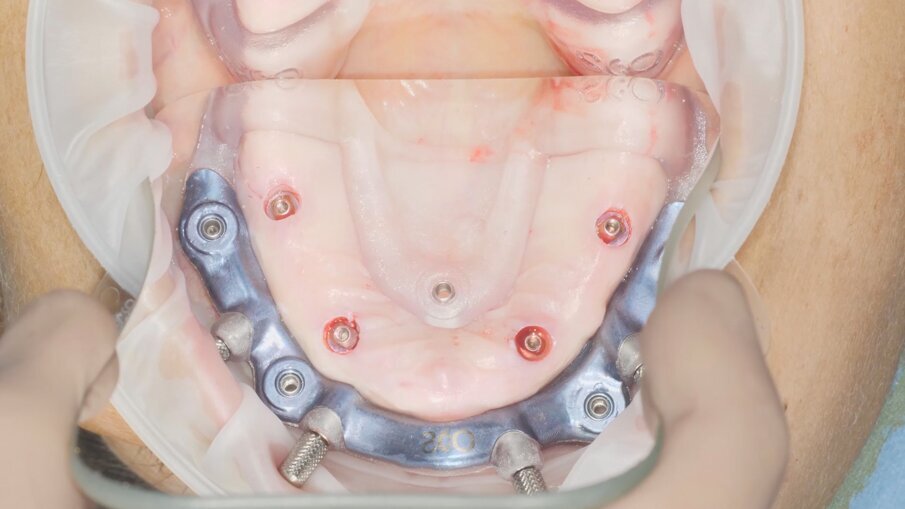

Fase chirurgica Entrando nel vivo delle fasi chirurgiche, vediamo in Fig. 9 l’alloggiamento dell’indice di posizionamento per il fissaggio della dima base. È molto importante effettuare un primo try-in prima dell’anestesia così da accertare il corretto alloggiamento della protesi su tessuti privi di gonfiore. Dopo l’anestesia si procede a verificare nuovamente la posizione andando a comprimere le zone dove può essersi accumulato liquido anestetico. Verifichiamo il corretto alloggiamento del sistema Pcube attraverso le finestre di ispezione e verificando l’intercuspidazione con l’arcata antagonista. Rimosso l’indice di posizionamento (Fig. 10) possiamo apprezzare l’ampio accesso al campo chirurgico offerto dalla dima base e procedere con la fase di scansione intraoperatoria (Trios 4 – 3Shape). Abbiamo infatti deciso per fini documentali di procedere a una serie di scansioni per verificare in modo continuativo l’effettivo grado di precisione del trattamento rispetto alla pianificazione digitale grazie alla sovrapposizione dei file .stl (Fig. 11). Procediamo quindi con il fissaggio della dima chirurgica in titanio anodizzato, sempre sfruttando i sistemi di ancoraggio della dima base (Fig. 12). L’utilizzo di un mucotomo è il passaggio preliminare alla preparazione del sito implantare, non prevedendo, in questo caso, l’apertura di un lembo. Questa scelta si lega alla buona disponibilità ossea e di tessuto cheratinizzato della paziente; tuttavia, la finestra di accesso al campo operatorio garantita dalla dima base del sistema Pcube permette approcci a lembo aperto senza prevederne la rimozione (Fig. 13).

Il posizionamento implantare segue un ordine contrapposto, prestando attenzione nella fase di avvitamento a non arrivare subito a fine battuta sulla dima implantare (Figg. 14, 15). I mounter montati sugli impianti monofasici con MUA integrato devono essere inseriti all’interno delle cannule della dima implantare, prima di procedere a ricercare l’accoppiamento tra il mounter stesso e lo scasso sulla dima che permette l’accesso del cacciavite per il rilascio (Figg. 16-18). Questo accorgimento ci dà la conferma ulteriore del corretto posizionamento degli impianti con MUA integrato da 17° di inclinazione e non è previsto per i dispositivi con MUA integrato con inclinazione 0°. Una volta rimossi i mounter possiamo disancorare la dima chirurgica dalla dima base (Fig. 19). La Fig. 20 mostra l’emergenza della componente protesica integrata degli impianti attraverso la mucosa. Sui MUA vengono quindi posizionati gli abutment in titanio preparati dal tecnico che ha potuto seguire la chirurgia sul modello (Fig. 21).